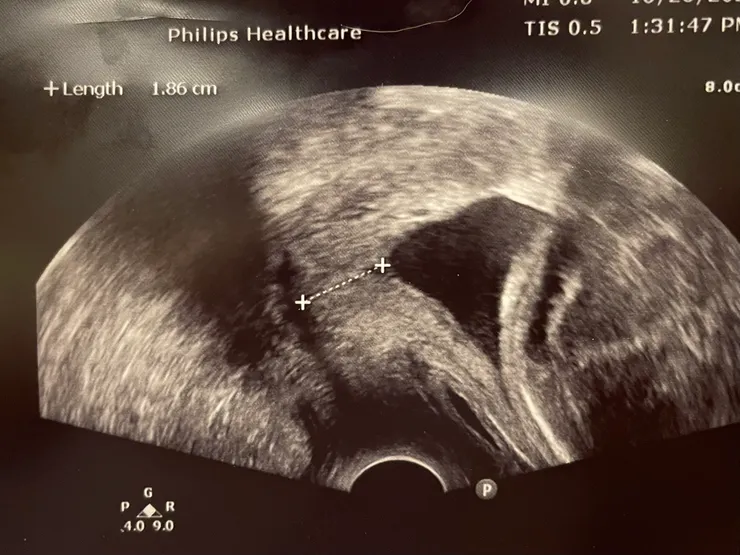

探頭進入陰道以後,醫生量測了一段長度,發現只剩下1.86cm... 一開始看不懂超音波畫面的我,還搞不清楚狀況,經過醫生說明才知道子宮頸內口已經打開,變成一個漏斗的形狀,而寶寶的頭就在子宮頸內口上,看起來狀況非常不妙。